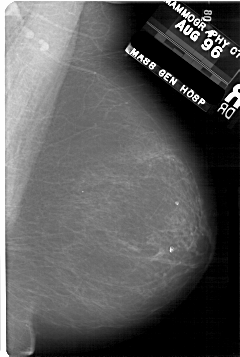

A_1731_1.RIGHT_MLO

RIGHT_MLO LINES 5341 PIXELS_PER_LINE 3586 BITS_PER_PIXEL 12 RESOLUTION 43.5 NON_OVERLAY